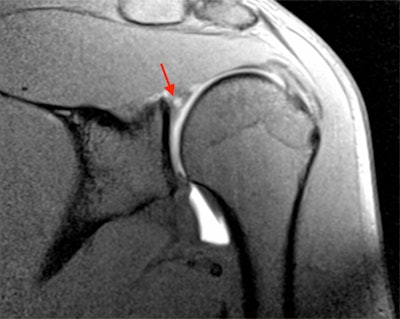

Typical throwing shoulder injuries are SLAP (superior labrum anterior and posterior) tears, which may be associated with internal impingement of the shoulder seen with high-velocity movement of the upper arm. In view of the U.S.'s greater experience of these particular injuries, the U.S. radiologist's angle (given by Dr. Lynne Steinbach from the University of California, San Francisco) should highlight what to look for on a shoulder MRI.